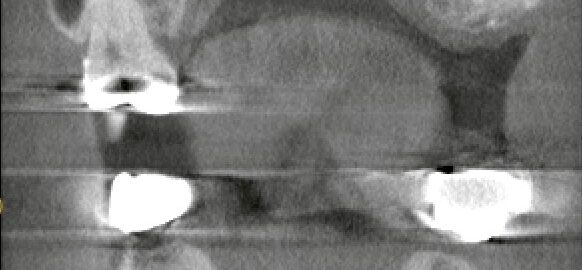

サイナスリフトとは?上顎インプラントで骨が足りないときに行う骨造成治療をわかりやすく解説

本日は、サイナスリフト(上顎洞底挙上術)について解説します。 インプラント治療は「インプラントを入れる」ことが注目されがちですが、 本質はその前段階にあります。 それは、 インプラントを長期的に支えられるだけの骨があるか … 続きを読む サイナスリフトとは?上顎インプラントで骨が足りないときに行う骨造成治療をわかりやすく解説